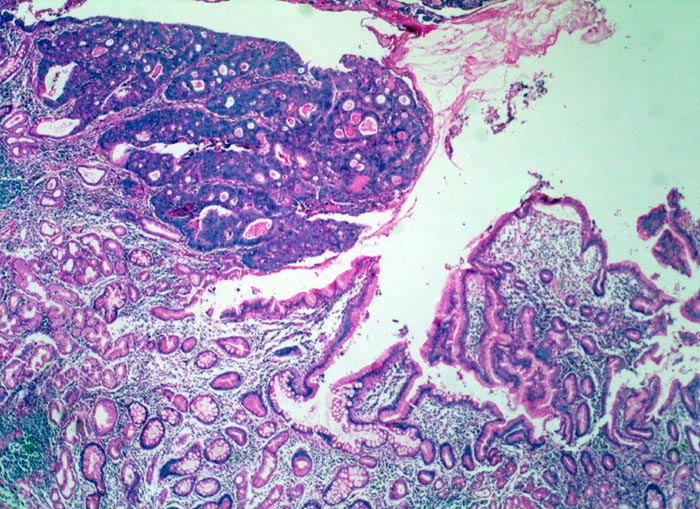

PathoPic – image database / PathoPic ID 5057 - Magenfrühkarzinom

Magenfrühkarzinom

Die Lamina propria der Antrumschleimhaut ist entzündlich infiltriert. Neben Schleimdrüsen vom Antrumtyp finden sich zahlreiche metaplastische Drüsen mit Becherzellen. Die Mukosa wird von einem polypoiden scharf begrenzten Tumor infiltriert. Aufgrund der vergrösserten Kerne ist das Tumorgewebe deutlich basophiler als die Drüsen der Mukosa. Der Tumor bildet dos à dos liegende Drüsen (kribriformes Wachstumsmuster).

Polypoider Tumor im Magenantrum.

Intramukosal lokalisierte Karzinome des Magens können im Gegensatz zu Adenomen des Kolons in die Lymphknoten metastasieren, obwohl das Karzinom die Lamina muscularis mucosae noch nicht durchbrochen hat.